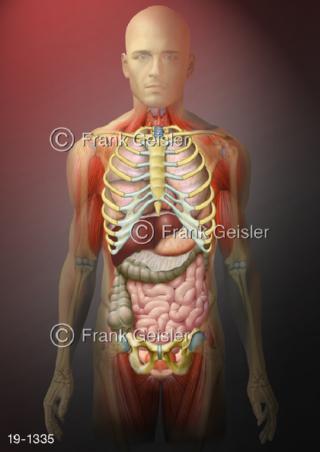

Bildergalerie Medical Art

Bilder zu Medical Art und Anatomie-Art, visuelle Darstellung medizinischer Inhalte künstlerisch umgesetzt, medizinisches Fachwissen als künstlerische Gestaltung für die Ausbildung, zur Patientenaufklärung und zur wissenschaftlichen Kommunikation, als künstlerische Dekoration in Gesundheitseinrichtungen und Arztpraxen